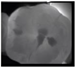

The use of near-infrared transillumination (NIRT) for early carious lesions detection has been described for more than a decade [14,17]. The enamel appears highly transparent when illuminated using NIRT and dentine appears darker than enamel because it scatters light more strongly. During the caries process, micropores are formed in the lesion due to the partial dissolution of the individual mineral crystals. These small pores behave as scattering centers, strongly scattering visible and near infrared light. Carious lesions appear dark because they scatter and absorb light more than surrounding healthy tissue [17,18,19]. Real-time images are displayed on a monitor and can be stored to allow monitoring. [20,21] The area and contrast of occlusal lesions in NIRT images can be correlated with lesion severity, and lesions that penetrate into dentine have significantly higher contrast than those in the enamel [18,22]. Several studies have shown NIRT to have higher sensitivity than BW to detect both proximal and occlusal carious lesion [23,24,25,26,27]. NIRT has also shown higher inter-examiner and intra-examiner reliability than BW [22,28,29]. The device DIAGNOcam (Kavo, Biberach, Germany) used in this study is the first marketed device that uses NIRT technology and has been tested in multiple studies [21,30,31,32].

In the present clinical study, ICDAS scores of occlusal surfaces based on clinical photographs were compared to scores based on NIRT images and digital intra-oral radiographs. The results show that more early occlusal lesions were detected using NIRT followed by clinical images, while BW scores showed mostly sound surfaces at both examinations (first and second assessments) as shown in Table 3.

The low percentage of carious lesions detected on BWs in our study corroborates the finding of previous studies concerning occlusal carious lesion detection on radiographs. When occlusal lesions are detected on radiographs they usually have reached the middle third of the dentine [41]. Previous studies have shown that BWs have negligible diagnostic value to detect enamel carious lesions and occlusal superficial dentine carious lesions [42,43]. NIRT could therefore be a good adjunct to clinical examination for detecting early occlusal caries. Several studies have suggested that combining the visual examination with another method could improve the accuracy of occlusal carious lesions detection [44,45]. These studies also confirmed the findings of our study.